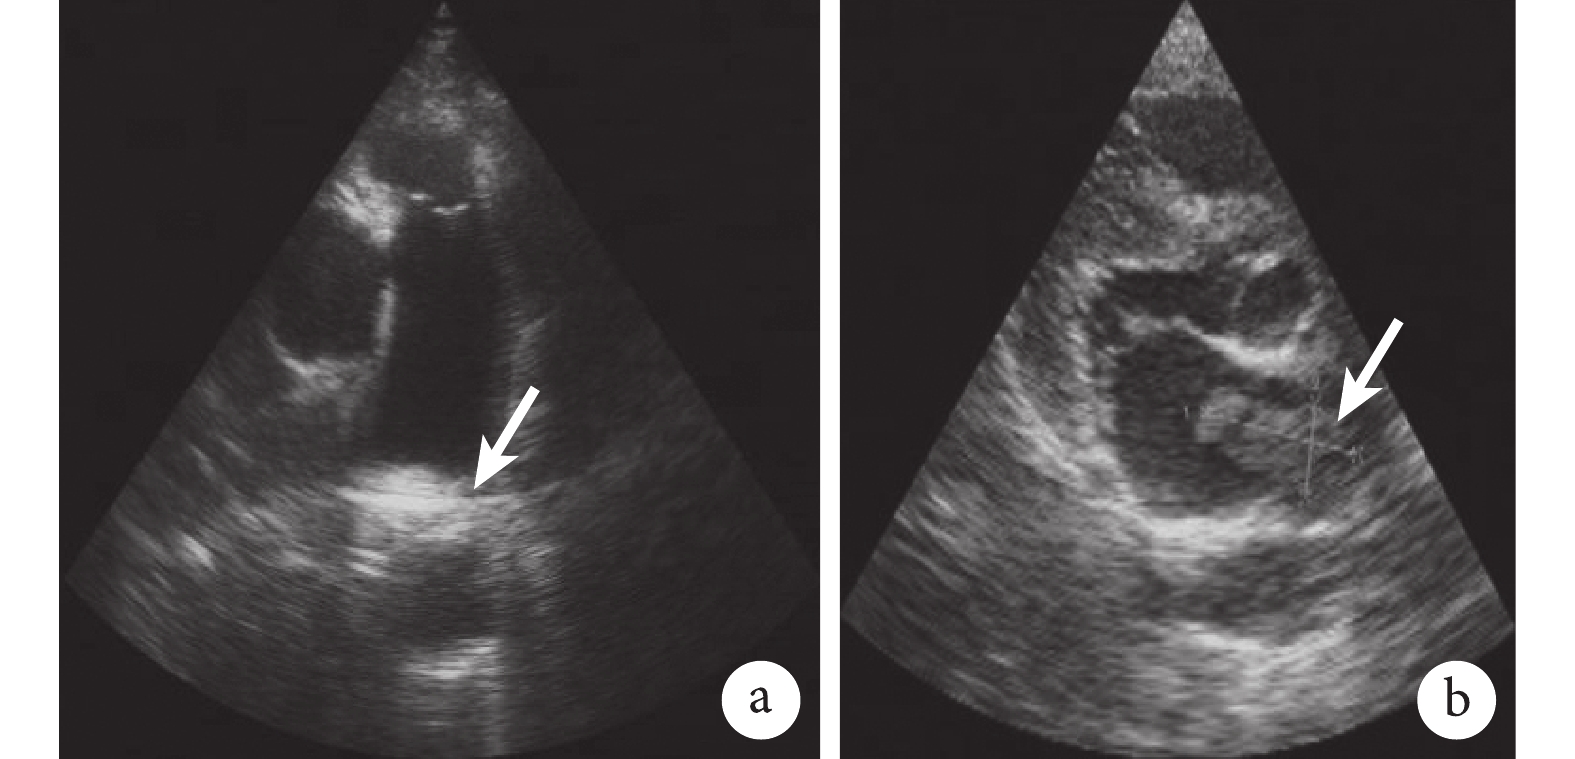

左肺動脈起始段管腔不完全栓塞(a 中白箭);左心房內附壁團塊,大小約31 mm×19 mm,無活動度(b 中白箭)。